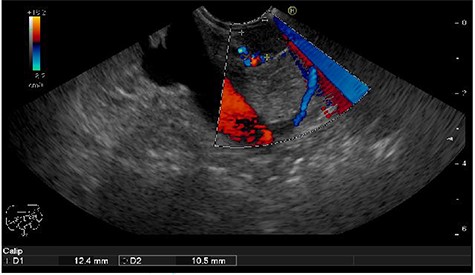

We present the case of 46-year-old female patient suffering from spontaneous hypoglycemia. She was admitted to our hospital due to worsening clinical symptoms. At first, she underwent a 72-hour monitored fast and biochemical testing for endogenous hyperinsulinism, which proved positive. Once the other causes of spontaneous hypoglycemia were excluded, we started the process of localization of insulinoma. Then the patient underwent endoscopic ultrasonography (EUS) of pancreas with the find of hypoechogenic, well demarcated, hypervascular tumor in the head of pancreas size of 12.4 × 10.5 mm (Fig.1). Computed tomography (CT) examination of abdomen followed up and tumor of pancreatic head, corresponding with the diagnosis of insulinoma, was found (Fig. 2). It was located nearby pancreatic and biliary duct. Because of serious clinical symptoms, an early surgical treatment was indicated. Based on the evaluation of the surgeon to perform the less radical surgery, it was suggested to enucleate the tumor with preoperative stenting of pancreatic and biliary duct. Two days before the surgery, ERCP with insertion of pancreatic and duodenobiliary stent was performed (Fig. 3). With regard to the patient's preference and overweight, laparotomic approach was selected. Determination of the exact position of tumor was difficult, insulinoma was hardly palpable. We used intraoperative ultrasonography to identify the exact location of tumor (Fig. 4). Then the surgeon palpated the inserted stents and the insulinoma was identified intrapancreatically, 3–4 mm nearby pancreatic and bile duct. Enucleation of tumor was performed by harmonic scalpel (Fig. 5). During the surgery, the right position of stents was verified by touch. After enucleation, there was no presence of bleeding, the defect was filled with tissue glue (Fig. 6). Macroscopically, tumor was round shaped, well capsulated, size 1 cm (Fig. 7). During postsurgery period, the patient was stable and with no signs of complication. On the sixth postoperative day, endoscopic removal of pancreatic stent was carried out. Patient was discharged from the hospital on the eight postoperative day. Duodenobiliary stent was left in ductus choledochus for 1 month.

Hypoechogenic round shape tumor in the head of pancreas (between two marks)–EUS.